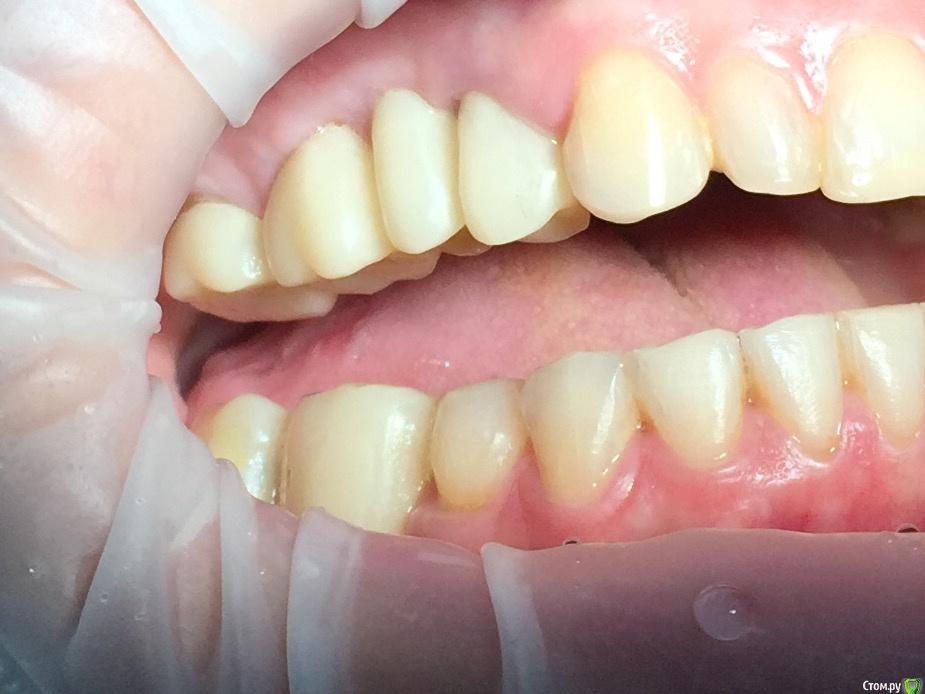

Глеб Митрофанов Опубликовано 12 сентября, 2015 Поделиться Опубликовано 12 сентября, 2015 (изменено) Направлена ортопедом , к которому пришла от другого хирурга и ортопеда , которые оперировали и изготавливали времянки соответственно . Пришла с просьбой - хочу сосочки ! Изменено 12 сентября, 2015 пользователем Глеб Митрофанов Ссылка на комментарий

Глеб Митрофанов Опубликовано 12 сентября, 2015 Автор Поделиться Опубликовано 12 сентября, 2015 А какой вопрос? С какой целью написали?Что возможно сделать , чтоб сделать максимально приближенное к желаемому ? Работа с мягкими тканями , времянками ?? Ссылка на комментарий

faity Опубликовано 12 сентября, 2015 Поделиться Опубликовано 12 сентября, 2015 пластика с бугров наверху, снизу полностью переделывать ортопедию и делать пластику с бугров. Гамборена вчера показывал как))) carlos показывает уже год 4 Ссылка на комментарий

Aquarius Опубликовано 12 сентября, 2015 Поделиться Опубликовано 12 сентября, 2015 Что возможно сделать , чтоб сделать максимально приближенное к желаемому ? Работа с мягкими тканями , времянками ??Если имплант не глушить, то по моему никак Ссылка на комментарий

Mane Опубликовано 12 сентября, 2015 Поделиться Опубликовано 12 сентября, 2015 снимаешь временную коронкупересаживаешь сст с бугра на тонкий формировательждешь месяцоцениваешьпротезируешь 2 Ссылка на комментарий